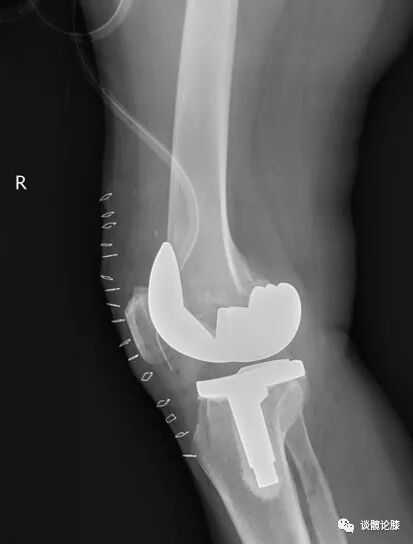

(3)重度内翻:骨膜下松解MCL浅层+普通假体(本人不推荐)

骨膜下松解MCL浅层+限制性假体(本人推荐)

內髁滑移截骨+普通假体(本人推荐)

外髁髁滑移截骨(推荐)

如果MCL功能不全,则使用上述平衡技术时,建议联合限制性假体